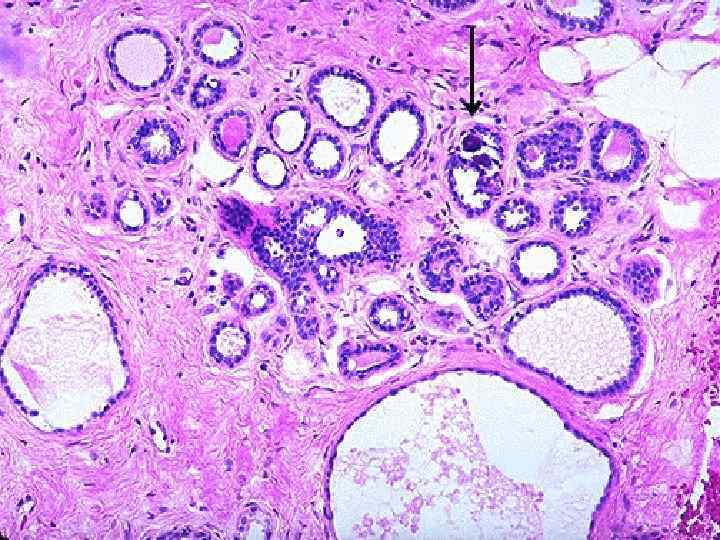

Дисгормональные болезни 1. Доброкачественная дисплазия молочных желез (мастопатия, фиброзно -кистозная болезнь) n непролиферативная форма n пролиферативная форма 2. Доброкачественные опухоли n внутрипротоковая папиллома n фиброаденома